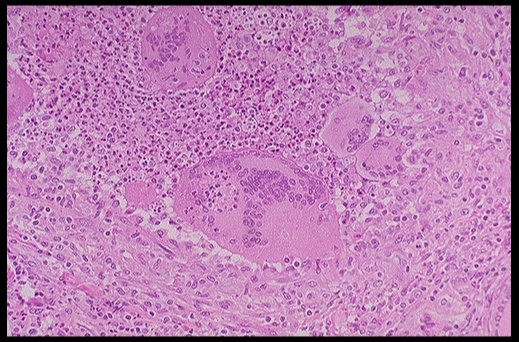

_On histology, a lymphocytic infiltrate with multinucleated giant cells surround fragments of colloid.

.,Subacute granulomatous thyroiditis. Note the giant cells, inflammatory cells and destruction of the thyroid follicules.